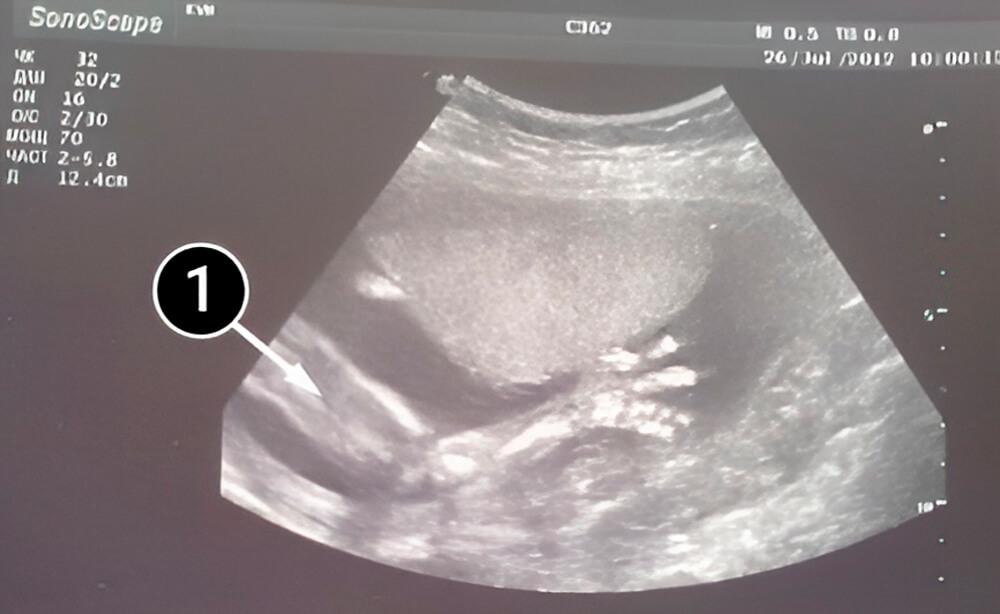

Lo que podemos ver en un ultrasonido

La imagen muestra la mano derecha del bebé. También son visibles la articulación del codo, el antebrazo y la mano, con los huesos de los dedos claramente marcados.